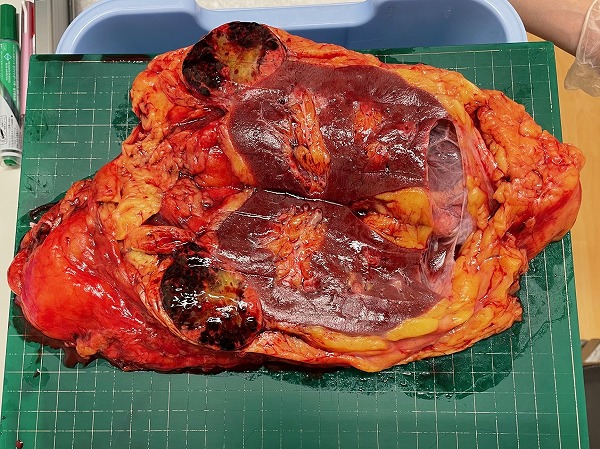

上の写真が切り取った右腎臓と癌。左がわの上と下にどす黒くなっているのが癌の腫瘍と思われる。「大きさは30㎝を超え、重さは3キログラムはあったと思う」と主治医は説明した。「あんなに大きく、重い腎臓は初めてでしたよ」と苦笑していた。撮影した美雨さんはこの日以来、口にするのは勿論、肉類に近付けなくなってしまって閉口しているという。 ごめんなさい~!♡☆